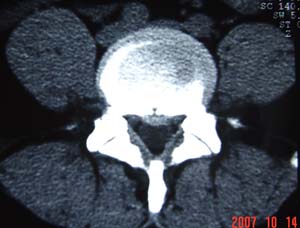

本人的片子,腰腿痛多年,时轻时重。请各位老师发表高见!

1.l4~5间盘膨出伴突出(中央型)

2.l5-s1后纵韧带钙化.